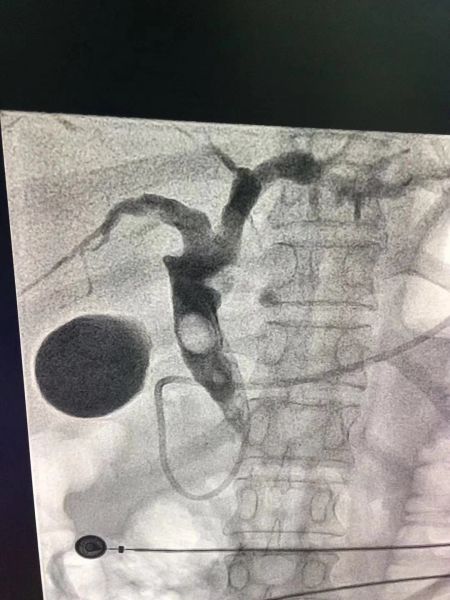

10月03日上午10点30分,肝胆外科二病区来了一个全身皮肤及眼珠发黄的患者,该患者因右上腹胀痛伴皮肤巩膜黄染1月入住肝胆外科二病区。完善检查提示:胆总管巨大结石,约2.0X1.5CM,总胆红素:615.2umol/L,直接胆红素543.8umol/L,皮肤巩膜重度黄染。患者梗阻时间长,随时可能出现急性梗阻性化脓性胆管炎(急性梗阻性化脓性胆管炎是危及生命的重症,如果救治不及时,将可能出现感染性休克,死亡率极高)。

肝胆外科二病区迅速对患者病情展开科内讨论。通过宋新科主任、姚本能病区主任、杨定华副主任等多位专家对病患身体状况评估及病情的分析谈论,决定实施多学科团队协作(MDT)治疗胆总管结石。第二天即邀请消化内科急会诊,征得家属同意后急诊行ERCP+ENBD术,术后黄疸逐渐下降,于一期减黄手术后1月,评估可行确定性手术治疗,于是进行了腹腔镜下胆总管探查取石+T管引流术。术后1周患者肝功能便恢复正常,痊愈出院。

针对此类患者,肝胆外科二病区联手消化内科,对多个重症胆管炎患者以“一期行ERCP+ENBD胆道引流,待感染控制后,二期行确定性手术”的治疗模式,成功实施救治,成果显著。这符合损伤控制原则,亦符合最新的急性胆道感染诊疗规范。

ERCP+ENBD术中图片